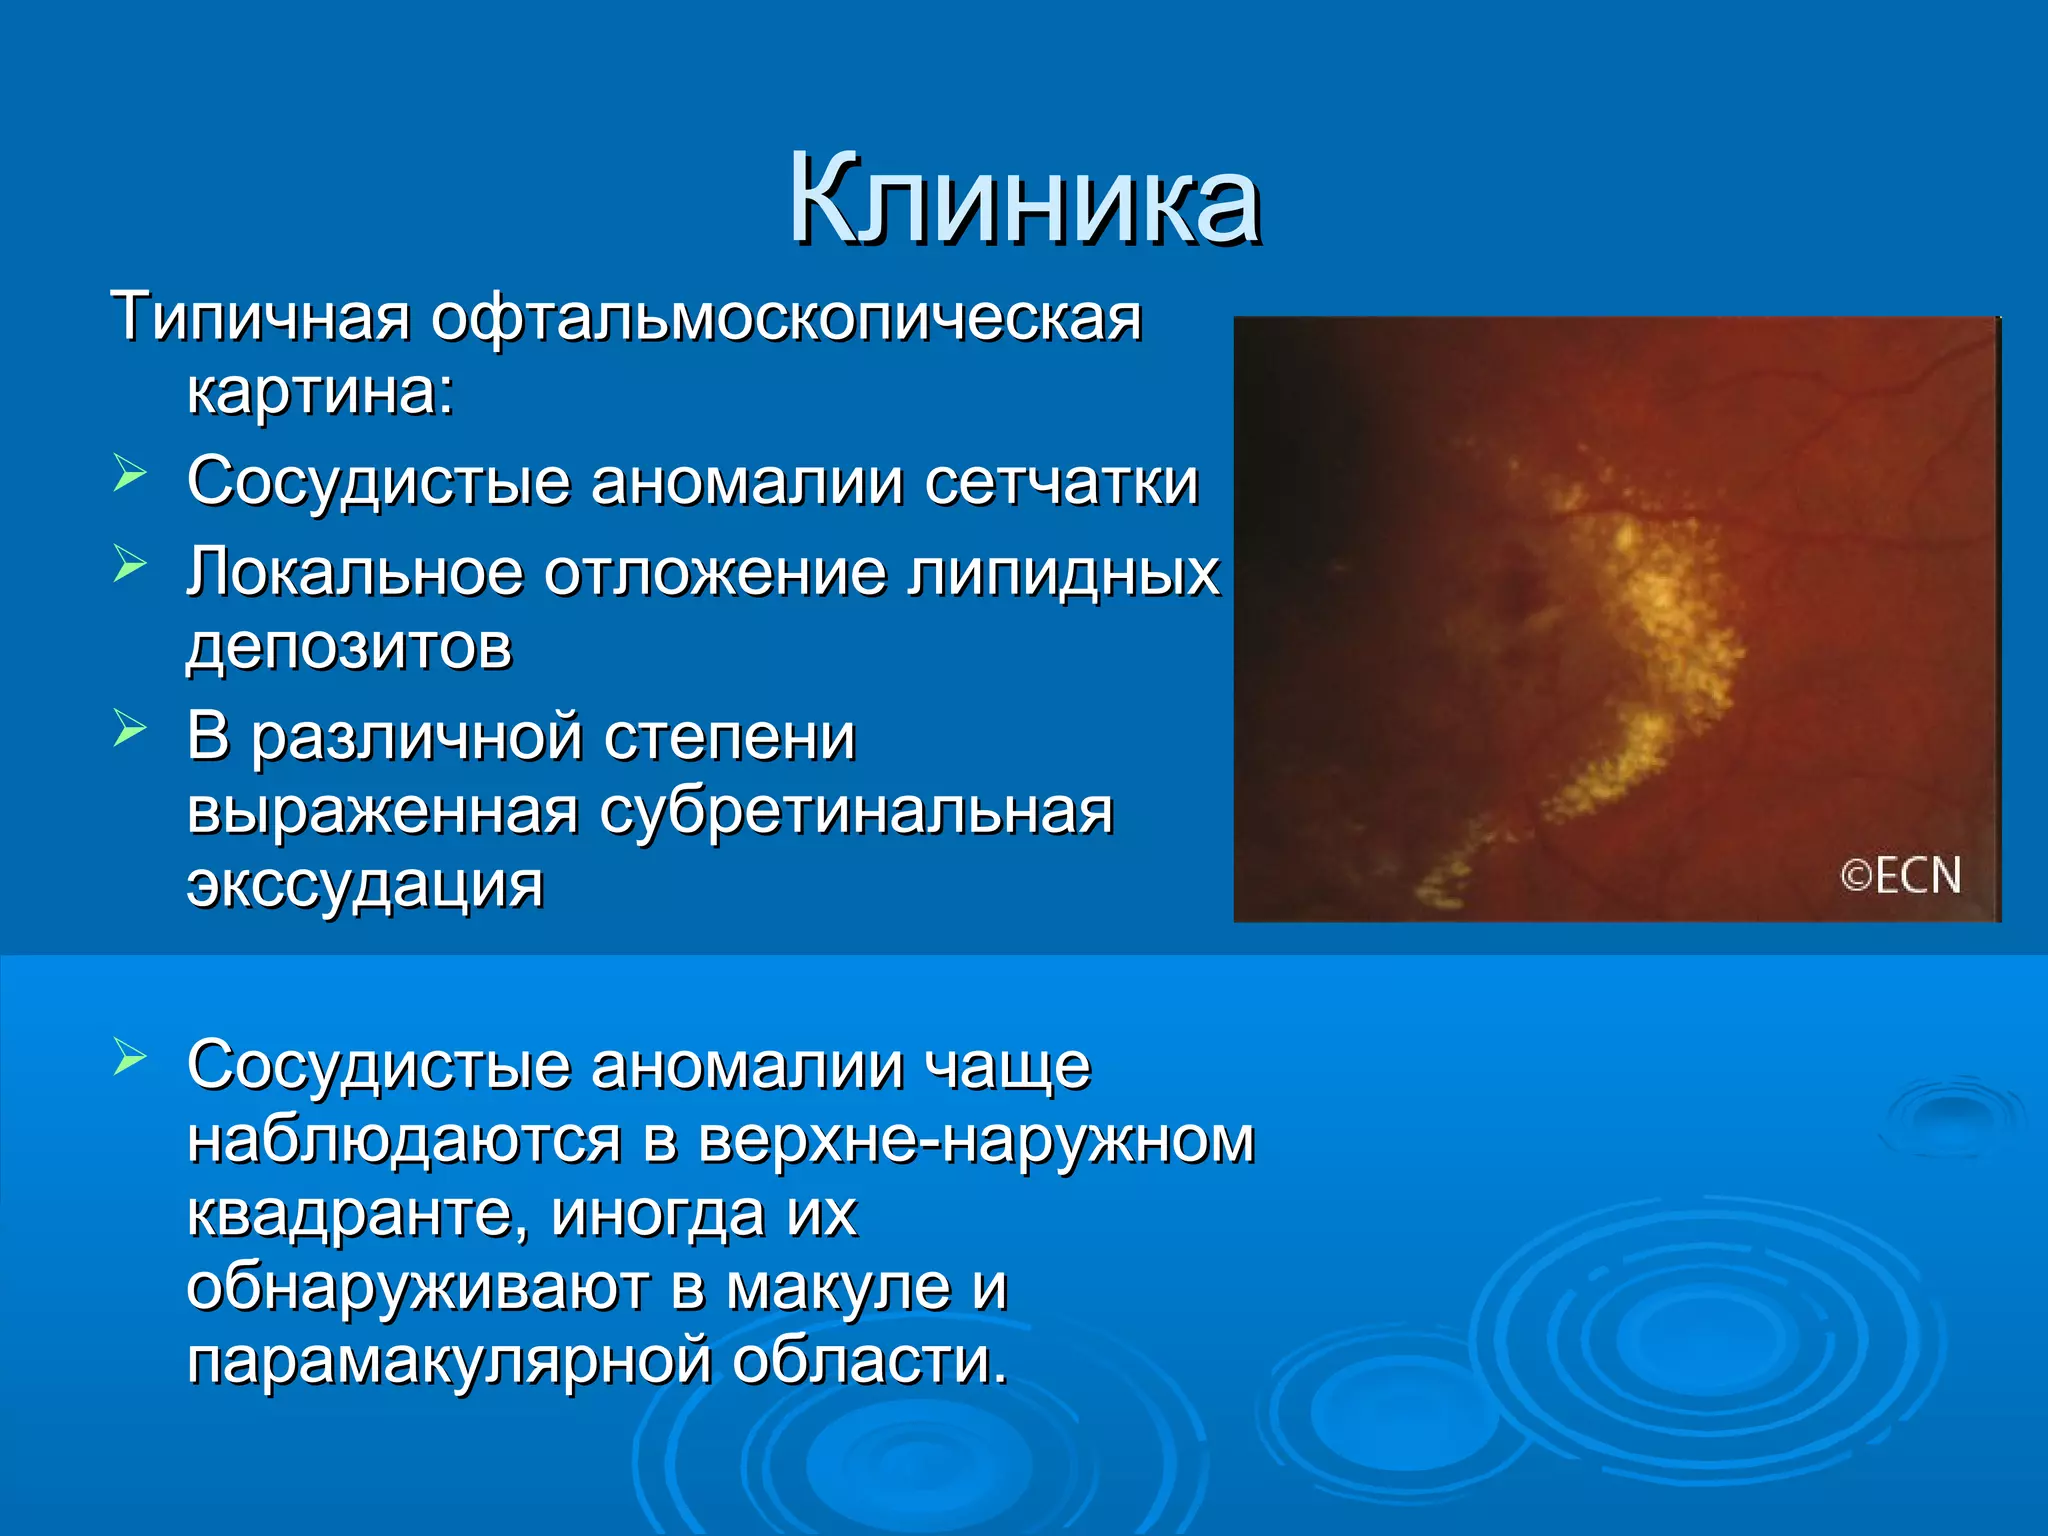

Болезнь Коатса - это идеопатическое заболевание, характеризующееся полиморфными изменениями сосудов сетчатки с массивной экссудацией, чаще всего у детей и подростков, с преобладанием среди мальчиков. Эпидемиология показывает, что заболевание проявляется, как правило, в возрасте 8-16 лет, но возможно его обнаружение и у взрослых. Основные проявления включают ретинальные аномалии, субретинальную экссудацию и постепенно прогрессирующую потерю зрения.